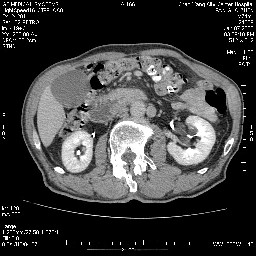

女,74岁,呕吐10余日

考虑来源于十二指肠水平段的恶性占位,侵及周围组织,特别是胰腺,可见区域淋巴结肿大,左侧下腔静脉畸形。

双肾多发小囊肿;左肾积水。

十二指肠水平段腔内占位伴梗阻,中等度较为均匀的强化,洗脱慢,区域淋巴结显示增多,符合腺癌表现。下腔静脉变异。

十二指肠降段扩张,水平段狭窄成鼠尾状,肠壁明显增厚,胰腺勾突增大成不均匀强化,其内可见低密度区,胆囊增大,1十二指肠水平段腺癌侵犯胰腺勾突可能大,2胰腺癌侵犯十二指肠(只有胆囊增大没有肝内外胆管扩张不好解释)代除外.

需除外12指肠水平段间质瘤。

十二指肠水平部腺癌伴梗阻并侵犯邻近结构。下腔静脉发育变异。

十二指肠降段扩张,水平段狭窄成鼠尾状,肠壁明显增厚,胰腺勾突增大成不均匀强化,其内可见低密度区,胆囊增大,1十二指肠水平段腺癌侵犯胰腺勾突可能大,2胰腺癌侵犯十二指肠 。

今日手术结果:胰腺钩突癌侵犯十二直肠,腹腔淋巴结转移.